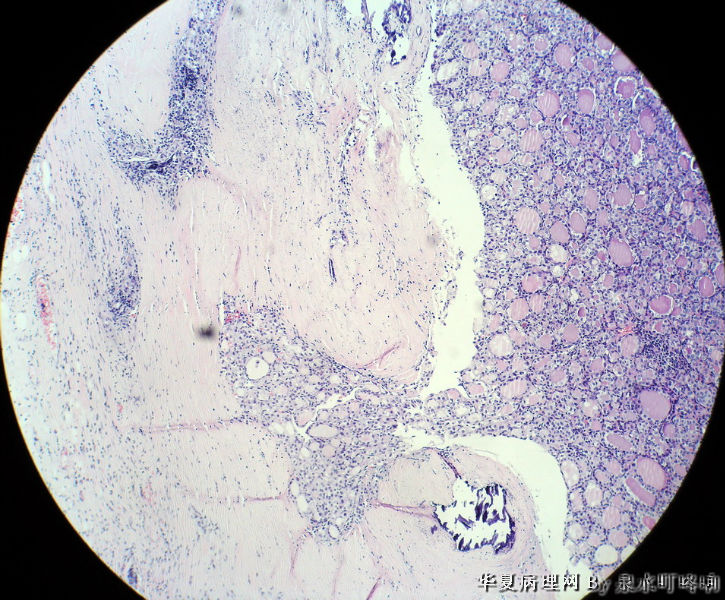

120212,女,55岁,左颈部肿物七年余。

大体:灰白肿物一个,大小约2.1×1.5×1.3厘米。表面光滑,包膜完整,切面灰白,部分包膜有钙化。

与手术医生沟通,肿物位于左颈部靠近甲状腺部位,比较浅(门诊手术),手术医生认为是淋巴结部位。

厚包膜、蕈状浸润----滤泡癌。

甲状腺滤泡性肿瘤,可见包膜及血管侵犯,考虑滤泡癌。

甲状腺滤泡状癌,有包膜浸润及血管内瘤栓